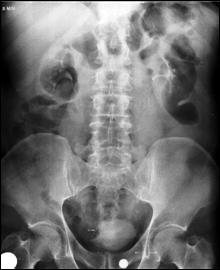

4.1. Radiografia renovezicala simpla si UIV raman examenele de baza pentru diagnosticul etiologic al oricarui pacient cu hematurie. Tumorile vezicale au drept semn radiologic cardinal imaginea lacunara pe cistograma urografica. Tumorile infiltrative pot induce modificari ale supletii peretelui vezical, care devine rigid, inextensibil, retractat etc. in zonele patologice. Ureterohidronefroza sau rinichiul mut sunt rezultatele invaziei si obstructiei ureterelor intramurale induse de tumorile solide, infiltrative (Fig.27,28,29).

Figura 28. Imagine

lacunara de 2,8/2 cm, in aria vezicii urinare, sugerand tumora

vezicala.

Figura 33. a) Imagine lacunara voluminoasa, ocupand

hemivezica dreapta; rinichi drept mut UIV; b) Imagine lacunara in hemivezica

dreapta; c) Rigiditate la

nivelul hemivezicii drepte; d) Cistouretrografie intramictionala

demonstrand imagine lacunara in hemivezica stanga.